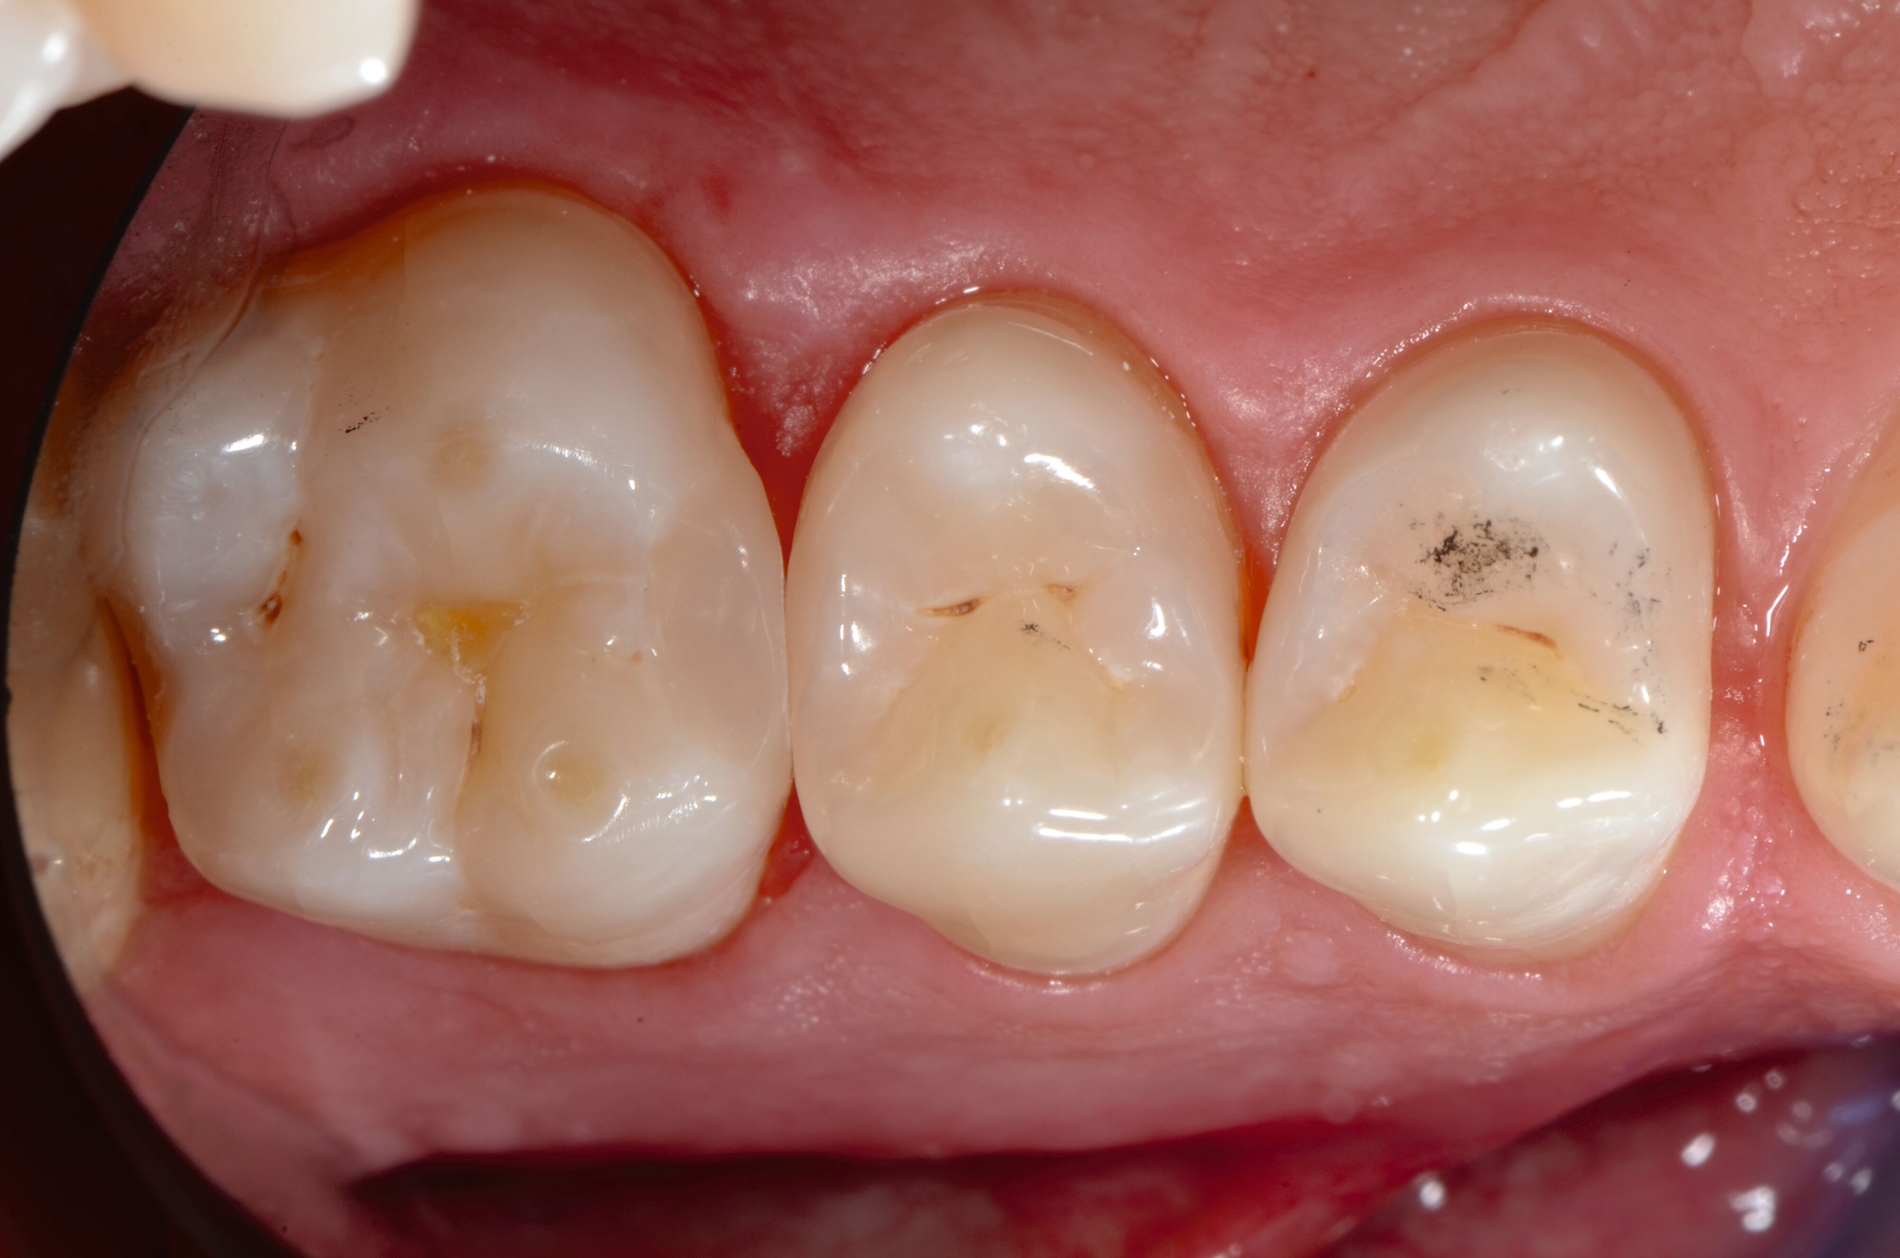

Die Kariesexkavation ist ein wichtiger Eckpfeiler eines erfolgreichen Restaurationsprozesses. Es gibt zwei grundsätzliche Ansätze: die non-selektive Exkavation, bei der das gesamte kariöse Gewebe bis zur gesunden Zahnsubstanz in der Kavität entfernt wird, und die selektive Exkavation, bei der das kariös veränderte Gewebe in der Nähe der Pulpa belassen wird, um das Expositionsrisiko dieser zu minimieren [Barros et al., 2020]. Außerdem können diese Methoden als schrittweise (zweistufige) Kariesentfernung kombiniert werden [Schwendicke et al., 2021]. Weitere vitalerhaltende Maßnahmen wie Überkappungen oder (partielle) Pulpotomien wurden in dieser Leitlinie nicht evaluiert.

Sowohl selektive als auch nicht-selektive Kariesexkavationsmethoden haben sich als effektiv erwiesen. Die selektive Kariesentfernung zeigt jedoch bessere Ergebnisse bei der Erhaltung der Pulpa in tiefen Läsionen. Ein systematisches Review stellte keinen Unterschied im Restaurationserfolg über zwei Jahre zwischen der selektiven und der schrittweisen Kariesentfernung fest, betonte jedoch die Überlegenheit des selektiven Ansatzes hinsichtlich einer geringeren Pulpaempfindlichkeit [Hoefler et al., 2016]. Eine weitere Metaanalyse fand ebenfalls keinen signifikanten Unterschied im Restaurationsüberleben, verzeichnete jedoch bei der selektiven Methode weniger Pulpaeröffnungen [Li et al., 2018]. Ein Cochrane-Review kam zu dem Schluss, dass die selektive oder schrittweise Entfernung von kariösem Gewebe bei tiefen Läsionen wirksamer ist als die nicht-selektive Methode, wenngleich die Evidenzqualität meist als gering eingestuft wurde [Schwendicke et al., 2021]. Weitere Übersichtsarbeiten unterstützen ebenfalls das geringere Risiko einer Pulpaexposition und damit verbundener Symptome bei selektiver Kariesentfernung, insbesondere bei pulpanahen Läsionen [Barros et al., 2020; Schwendicke et al., 2013a; Schwendicke et al., 2013b].

Die Empfehlung lautet daher, bei pulpanahen Läsionen eine einzeitige selektive Kariesentfernung der schrittweisen oder non-selektiven Kariesentfernung vorzuziehen.